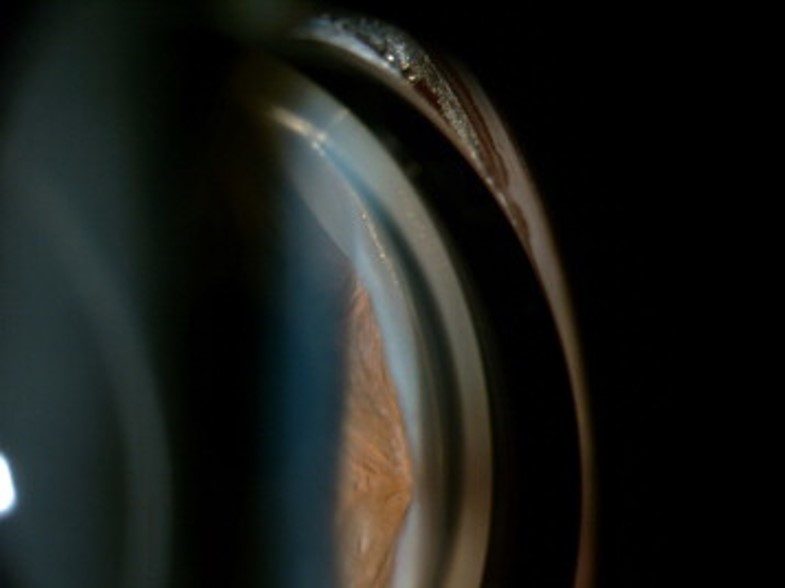

2) 주변부 홍채앞 유착 Peripheral Anterior Synechia, PAS

주변홍채앞유착, Peripheral Anterior Synechia, PAS는

섬유주소대에 Aiming 한 레이저의 광응고반이 크거나, 홍채 주변부에 닿음으로서,

혹은 그렇지 않더라도, 레이저조사를 받은 부위의 염증으로 인해

주변부 홍채에 달라붙어서 유착되는 경우입니다.

이때는 ALT를 시행한 광응고반의 위치와 일치하게 독립적으로 텐트모양으로 융기된 홍채를 볼수 있습니다.

섬유주 중에서 홍채에 가까운 부분 즉, Posterior TM 에 가깝게 레이저를 하는 경우, PAS의 가능성이 커집니다.